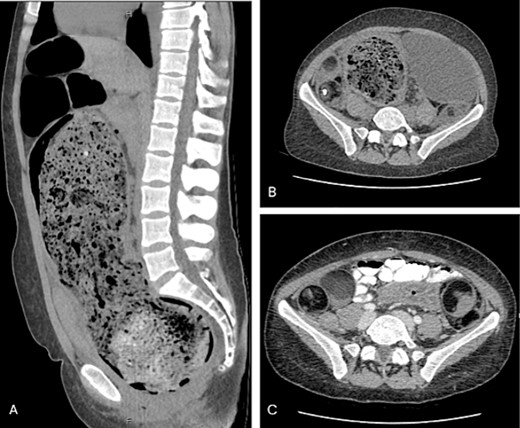

A CTAP demonstrated gross rectosigmoid distension (sigmoid colon 107 mm × 158 mm × 325 mm) with significant faecal loading (Fig. 1), progressed from previous imaging in 2014. There was no evidence of a volvulus, obstructing mass, or perforation. The chronicity of her presentation raised the possibility of AHD. Furthermore, the large bowel distension had caused partial bladder obstruction, with right-sided hydronephrosis. The CT also revealed bilateral heterogenous pelvic masses (right side measuring 83 mm × 39 mm × 87 mm, left side measuring 46 mm × 60 mm × 69 mm) suggestive of bilateral dermoid cysts, which was confirmed with an inpatient pelvic ultrasound.

(A) Sagittal view of grossly distended bowel with faecal loading; (B) axial view of dilated distal bowel; (C) axial view of bilateral dermoid cysts.